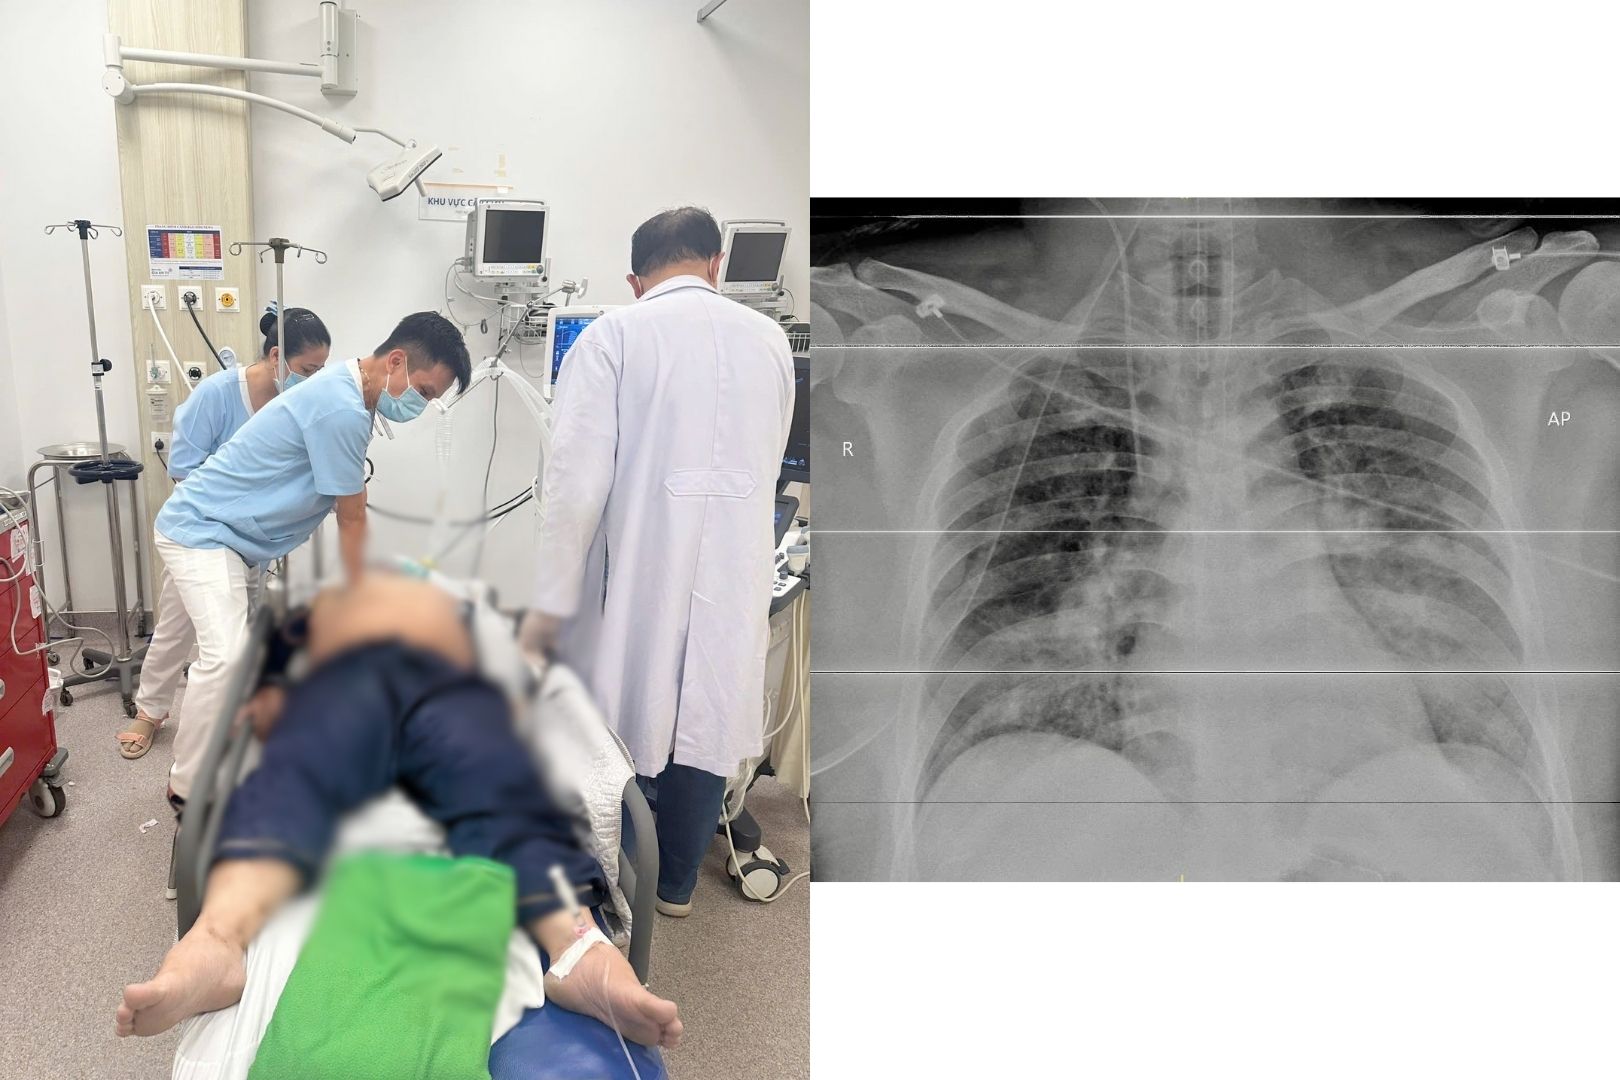

Bệnh ung thư và đột quỵ được xem là 2 bệnh hiểm nghèo đặc biệt nguy hiểm và đang có dấu hiệu gia tăng. Gần đây, người ta còn thấy rằng 2 “sát thủ” này còn có mối liên quan chặt chẽ với nhau, theo BS.CK1 Trần Thị Mai Uyên – Trưởng khoa Nội thần kinh – Đột quỵ, Bệnh viện Gia An 115.

Mối liên quan giữa bệnh ung thư và đột quỵ đã được đề cập trên thế giới. Bệnh đột quỵ gây ra sự tàn phế nặng nề cho bệnh nhân mắc bệnh ung thư, trong khi đó bệnh ung thư làm tăng nguy cơ bị đột quỵ.

BS.CK1 Trần Thị Mai Uyên – Trưởng khoa Nội thần kinh – Đột quỵ, Bệnh viện Gia An 115 chia sẻ về mối liên hệ giữa bệnh ung thư và đột quỵ.